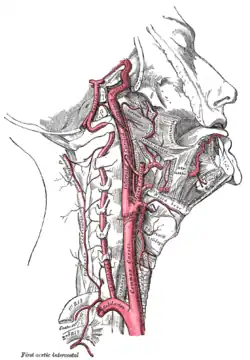

The internal carotid artery is a terminal branch of the common carotid artery; it arises around the level of the fourth cervical vertebra when the common carotid bifurcates into this artery and its more superficial counterpart, the external carotid artery.

The cervical segment, or C1, or cervical part of the internal carotid, extends from the carotid bifurcation until it enters the carotid canal in the skull anterior to the jugular foramen.

At its origin, the internal carotid artery is somewhat dilated. This part of the artery is known as the carotid sinus or the carotid bulb. The ascending portion of the cervical segment occurs distal to the bulb when the vessel walls are again parallel.

The internal carotid runs vertically upward in the carotid sheath and enters the skull through the carotid canal. During this part of its course, it lies in front of the transverse processes of the upper three cervical vertebrae.

It is relatively superficial at its start, where it is contained in the carotid triangle of the neck, and lies behind and medial to the external carotid, overlapped by the sternocleidomastoid muscle, and covered by the deep fascia, the platysma, and integument: it then passes beneath the parotid gland, being crossed by the hypoglossal nerve, the digastric muscle and the stylohyoid muscle, the occipital artery and the posterior auricular artery. Higher up, it is separated from the external carotid by the styloglossus and stylopharyngeus muscles, the tip of the styloid process and the stylohyoid ligament, the glossopharyngeal nerve and the pharyngeal branch of the vagus nerve. It is in relation, behind, with the longus capitis, the superior cervical ganglion of the sympathetic trunk, and the superior laryngeal nerve; laterally, with the internal jugular vein and vagus nerve, the nerve lying on a plane posterior to the artery; medially, with the pharynx, superior laryngeal nerve, and ascending pharyngeal artery. At the base of the skull the glossopharyngeal, vagus, accessory, and hypoglossal nerves lie between the artery and the internal jugular vein.

Unlike the external carotid artery, the internal carotid normally has no branches in the neck.